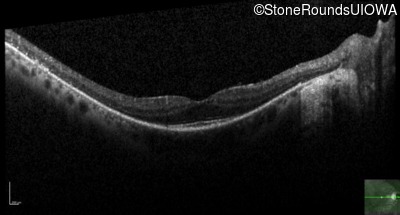

Optical Coherence Tomography - Left - 20/20 -2

Exemplar / OCT Stack

OCT Stack